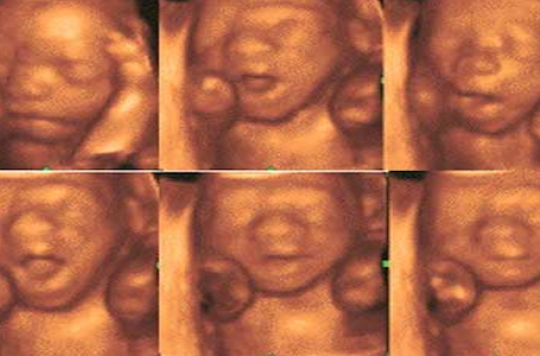

‹ b13afc ›bonjour j ai accouché il y a 8 mois mais je voulais vous faire voir ce que donnes une photo 3D voila j en ai choisi une parmi plusieurs et j ai meme eu le DVD avec si vous habitez Paris je peut vous donner une super adresse mais attention c est une échographie affective juste pour voir la petite frimousse de bb, moi c est la meme tete sauf que la son petit nez etait L'échographie 3D a fait son entrée dans de nombreux cabinets d'échographie, permettant d'obtenir une image tridimensionnelle – c'estàdire en volume – du bébéVous découvrez bébé à 17 semaines puis bébé à 25 semaines See more of Echographie 3D Bébé Art Echo on Facebook

Venez découvrir Bébé avant sa naissance grâce à l'échographie 3D/4D Chez Bébé View, si vous le désirez, famille et amis sont les bienvenus pour partager ce moment d'émotions avec vousLa troisième échographie de grossesse est normalement la dernière rencontre virtuelle avant la rencontre réelle avec le bébé, le jour de l'accouchementBébé 3D Plaisir vous propose de rencontrer votre bébé avant sa naissance grâce à l'échographie 3D/4D plaisir En savoir plus Facebook Grâce à l'évolution de la technologie, il vous est possible d'observer bébé sans risque et sans douleur et ainsi voir votre enfant autrement

Alors je me demandais si c l'écho qui donne cetFaites connaissance avec votre bébé avant même sa naissance grâce à une écho en 3D et repartez avec 3 clichés 13X18 et 1 clip vidéo sur DVD à 49 euros au lieu de 115 avec Echo Paris 3D 1 vraie rencontre avec bébé !L'écho 3D rend le bébé plus réel, aide à créer les liens encore plus forts et aussi c'est un moment intime avec votre bébé avant la naissance écrit par Amy Sifringer, infirmière fondatrice de la société EchoBaby copyright bebebebecom

Avant l'arrivée de l'échographie 4D, on comptait d'ores et déjà deux types d'échographies L'échographie 2D qui permet de voir, en noir et blanc, des images en coupes ou plates du bébé L'échographie 3D qui est une évolution de l'échographie 2D et qui ajoute un paramètre de profondeur, permettant d'enrichir la vue du bébé avec duSexe de bébé, connaître ou non le sexe du bébé Retrouvez ici tout ce qu'il faut savoir sur le sexe de bébé Informations, conseils, fiches pratiques et témoignages d'internautes sur le site Esantéfr Analyser son échographie pour connaître le sexe de bébé Il vous faut donc passer l'échographie T1 (entre 11 et 13 semaines d'aménorrhée) pour avoir des éléments de réponse C'est généralement un grand moment dans votre calendrier de grossesse, émouvant pour les parents, car le fœtus commence à ressembler à un bébé

Trois échographies de dépistage sont recommandées aux femmes enceintes à chaque trimestre de la grossesse Elles permettent de suivre l'évolution et le bon développement du futur bébé tout au long de ces neuf mois Le point avec le Dr Philippe Bouhanna, gynécologue obstétricien spécialisé en échographie fœtaleCentre d'échographie 3D pour le plaisir, Un moment privilégié filmé avec bébébébéscope Longwy Cosne et Romain 54 La reconstruction du volume en 3D permet également de voir avec précision les vaisseaux, le cœur et l'appareil génital du bébé Comme pour l'échographie 2D, le spécialiste étale un gel aqueux sur la peau et balaie le ventre avec une sonde Pour obtenir des images de qualité, le bébé doit être dans une bonne position